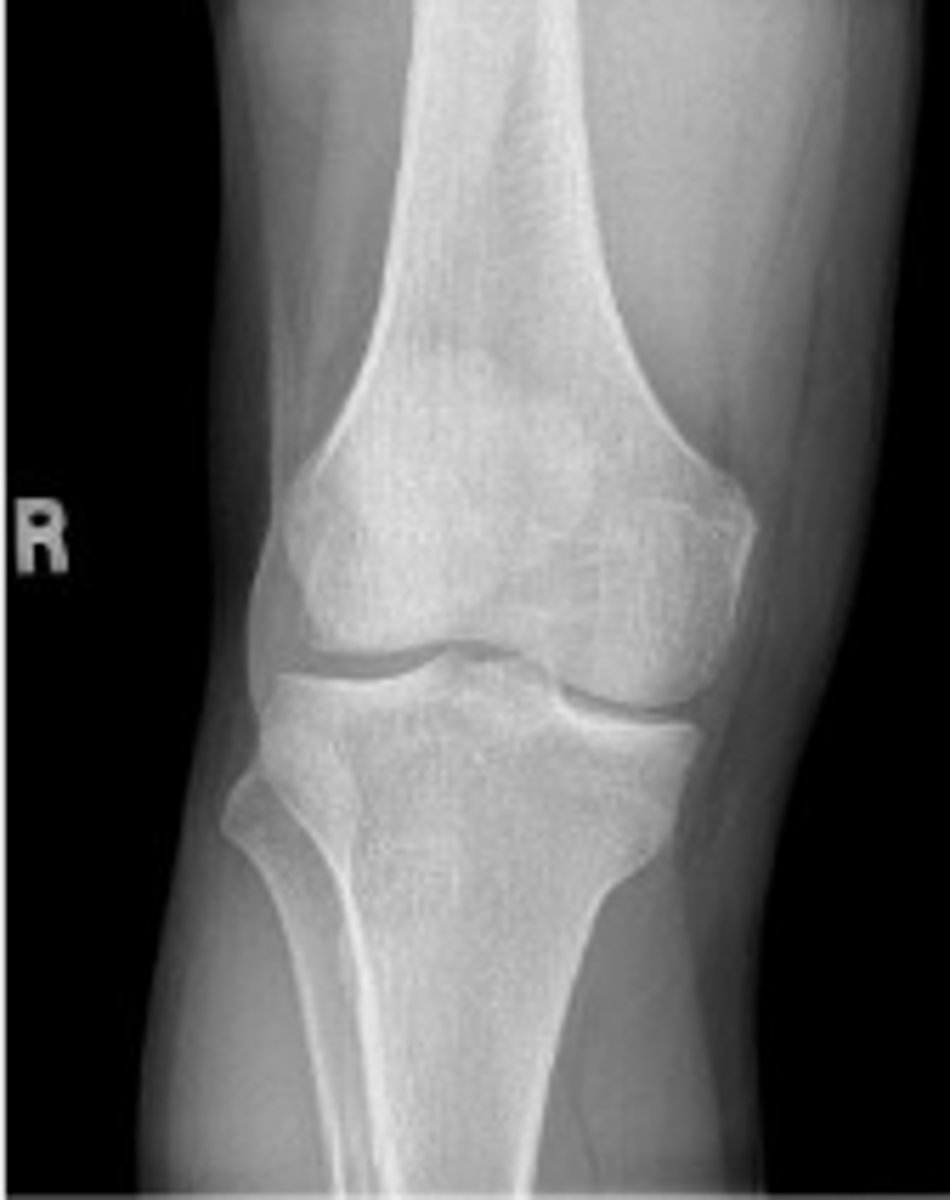

Right external oblique knee

What is the name of the radiographic view?